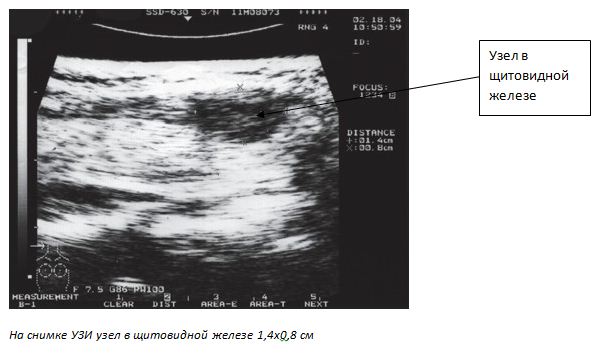

Наличие пальпируемого или видимого на УЗИ узла в железе является поводом для выполнения тонкоигольной биопсии.

- стандартный метод исследования — УЗИ лимфатический узлов и железы.